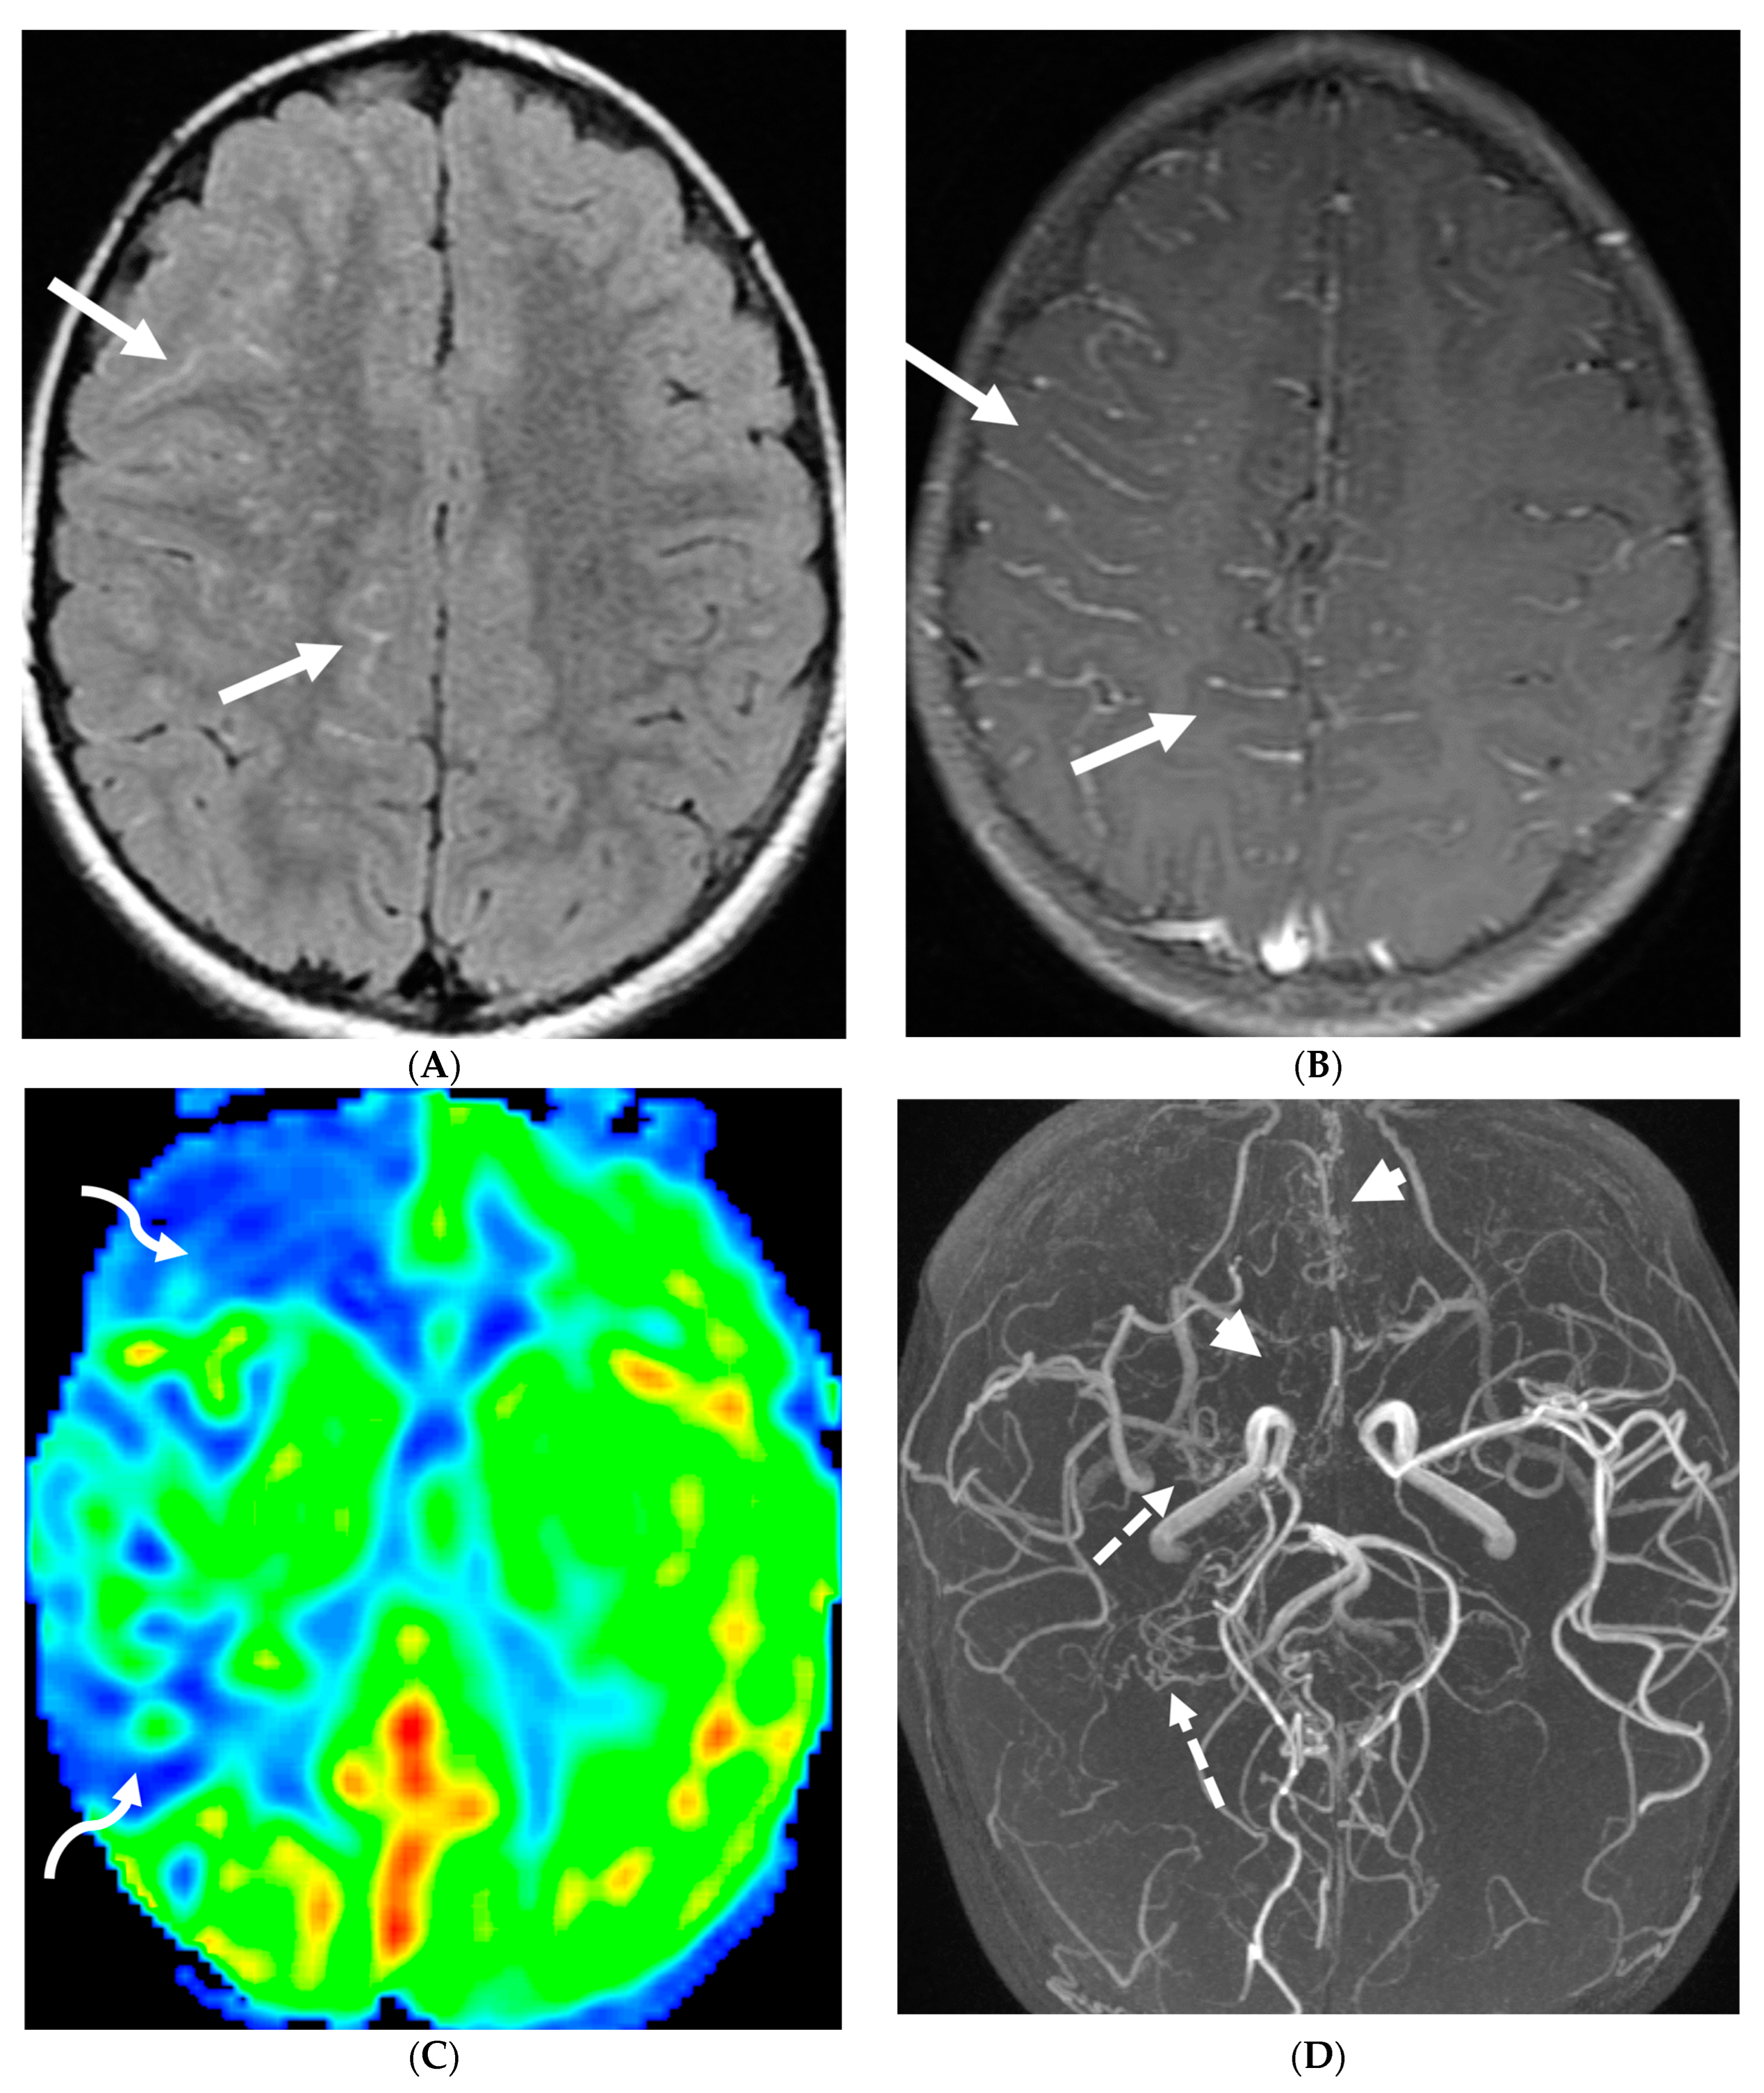

3.2. Neurosarcoidosis

Sarcoidosis is a systemic inflammatory disorder characterized by non-caseating granuloma formation [10,11,12]. Neurosarcoidosis (NS) is uncommon, detected on imaging studies in 15% of the patients, out of which only one-third of them present with clinical symptoms [10,13]. Granulomas, a hallmark of sarcoidosis, can infiltrate cerebral parenchyma, brain vasculature, and cranial nerves [14,15]. Parenchymal involvement leads to motor or sensory deficits, whereas predominant meningeal and subarachnoid involvement leads to cranial nerve deficiencies and vision changes [11]. Contrast-enhanced MRI of the brain and/or the spine is currently considered the standard of care for initial work-up and follow-up in NS [16].

Nodular or diffuse LME, primarily involving the basal meninges, is the most typical finding. It can further spread into the parenchyma via the perivascular spaces [17]. Most cases show focal involvement and are hypointense on T2WI with variable post contrast enhancement [18,19]. Nonenhancing white matter lesions (NEWM), although common, have been shown to have no symptomatic correlation [18]. Optic and facial nerves are frequently involved (Figure 3). The diagnosis of optic neuritis is crucial and regarded as an emergency due to its unfavorable prognosis if not promptly treated [20]. Occasionally [18,21,22], small vessel ischemia related cerebrovascular events occur which manifest clinically with progressive encephalopathy rather than a distinct large vessel stroke [13]. Other rare but important findings include spinal cord and hypophyseal involvement [23]. The mainstay of treatment for CNS sarcoidosis involves corticosteroids to suppress inflammation.

Figure 3.

18-year-old presented with headache, persistent vomiting and weight loss. History of sarcoidosis diagnosed 2 years ago. Axial Fluid Attenuated Inversion Recovery (FLAIR) (A), Axial T1 post contrast (B), Axial T1 inversion recovery post contrast (C) and Coronal Positron Emission Tomograpy (PET) scan (D): There is a heterogeneously enhancing ill-defined area of T2/FLAIR hyperintensity involving the medial aspect of the left globus pallidus (arrows), anterior aspect of the left thalamus and left hypothalamic region. Diffuse enhancement of the basal meninges, tentorium, throughout perisylvian sulci (arrow heads), along the infundibulum, and posteriorly at the craniocervical junction. There is also enhancement along optic nerve sheath (dashed arrows). Features are highly consistent with extensive neurosarcoidosis given the previous history of thoracic sarcoid. PET scan from 2 years earlier demonstrating avid uptake of radiotracer (curved arrows). Radiologically, the differential diagnosis includes tuberculosis and metastatic process. Patient made complete recovery after treatment for sarcoid.